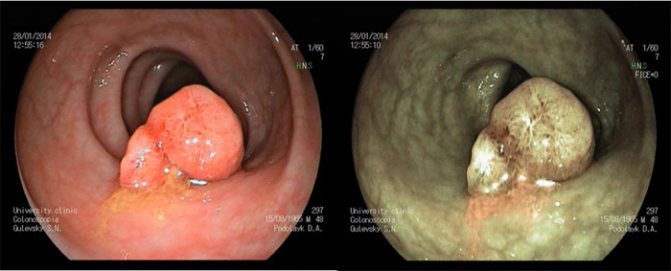

Представляем вашему вниманию макропрепарат (удаленный сегмент кишечника) вверху на макропрепарате – полип, внизу — злокачественная опухоль (рак). С каждым увеличением образования на 2 см риск возрастает на 20 %, именно поэтому даже самые маленькие полипы подлежат удалению. В идеальном варианте, чтобы не умереть от рака кишечника, необходимо проходить сигмоидоскопию при полипе сигмовидной кишки или колоноскопию, с подозрением на разрастания.

Аденоматозный полип толстой кишки — распространенная разновидность патологии, отличающаяся разрастанием красноватых узлов, размером около 3 см, имеет несколько типов:

Тубулярный аденоматозный вид — гладкие плотные полипы розового цвета, увеличивающиеся в размерах при прогрессировании заболевания. Ворсинчатый тип заболевания — красные новообразования множественного типа, имеющие ветвистую внешнюю форму большого размера (от 3 см), при несвоевременном лечении перерастают в злокачественную опухоль. Папиллярный тип заболевания по строению узла характеризуется прорыванием эпителия, что приводит к внутреннему кровотечению. Смешанная аденоматозная форма отличается образованием трубчатых и ворсинчатых плотных полипов.